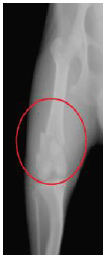

2. 中型犬の太ももの骨折(大腿骨骨折)

治療前のレントゲン写真です。 太ももを正面から見た図ですが、骨が折れているのが分かります。(赤丸) |